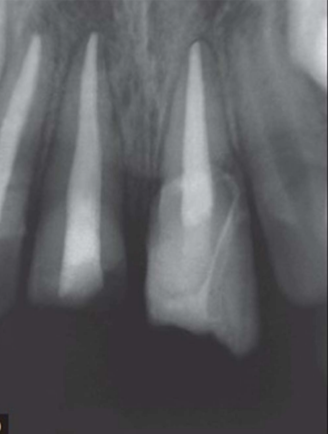

radiographic report

A

21 and 11 - can see fracture on 21

RCT - adequate down to apex and no voids/air bubbles, 11 GP exposed clinically - could expose to bacteria and saliva - inadequate seal - may need redone

Periapical healthy - OK, PDL ligament widening on mesial 21, not PA lesion on 11 as can see PDL going round tooth

what if you saw this toth in a pt about to go into chemo tx and it has previously been RCT

GP exposed risk infection

If fit and healthy - maybe post crown